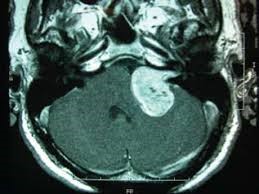

U dây thần kinh số VIII thường bắt nguồn từ lỗ ống tai trong. Có 4 thành phần đi qua lỗ ống tai trong, bao gồm: thần kinh tiền đình trên (SVN), thần kinh tiền đình dưới (IVN), thần kinh ốc tai (CN) và thần kinh mặt (FN). Đa số các trường hợp u dây VIII bắt nguồn từ thần kinh tiền đình trên và thần kinh tiền đình dưới, từ đây u phát triển ra góc cầu tiểu não (hình 1). Các khối u dây VIII lớn, nó có thể gây chèn ép thân não hoặc tiểu não và đôi khi có thể lan rộng lên hố sọ giữa hoặc xuống thấp đến lỗ chẩm.

Hình 1. U dây thần kinh số VIII